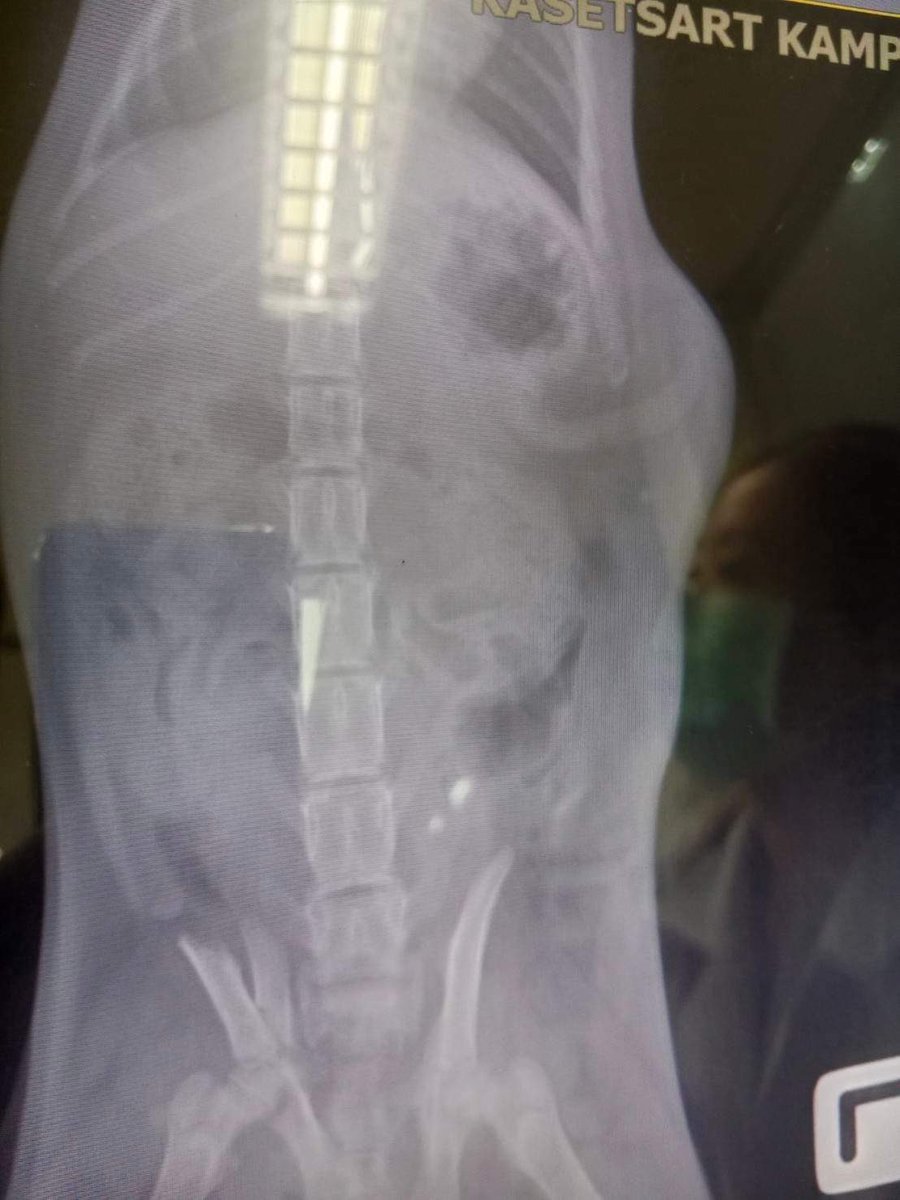

มาอีกแล้วจ๊ะพี่จ๋า รอบนี้เรามีแมวที่ประสบอุบัติเหตุต้องผ่าตัดกระดูกเพื่อรักษาชีวิต คล้ายเคส เสือขาวเลย ค่ะ จำเป็นต้องหาเงินให้เด็ก ๆ ก้อนใหญ่นิดนึง เสื้อยืดที่คุณเลือกเองได้เช่นเดิม อยากได้คำไหนบอกมาเลยค่ะ เราดีไซน์ฟ้อนท์ไว้รอแล้ว สีขาวสวยสุดแล้วค่ะ หรืออยากได้สีอะไรถามได้นะคะ